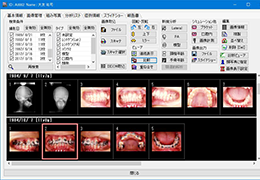

Load DICOM data directly from PACS, CD/DVD, USB, and local computer.

Easy to use patient search to locate patient data on your PACS.

Loads common non-DICOM file formats: NifTi (.nii), Visualization Toolkit (.vtk), and ANALYZE (.hdr).

Designed mainly for CT and MR DICOM modalities.